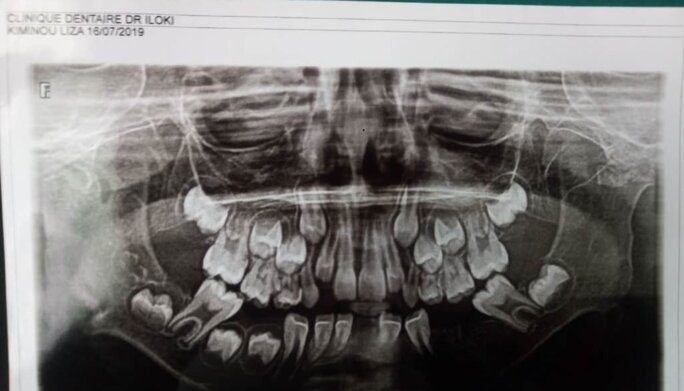

Notre jeune fille Lisa Kiminou Nganga devient le visage de la mauvaise gestion du gouvernement congolais. Nous espérons qu’ils baisseront de honte les yeux lorsqu’ils la verront.

Agrandissement : Illustration 2

Plus rien ne marche au Congo-Brazzaville au point où les enfants (notre relève) tels que Lisa Kiminou Nganga ne peuvent pas être pris en charge par le gouvernement congolais pour des maladies nécessitant une évacuation sanitaire ou pouvant être traitées sur place. Qu’a fait le peuple congolais pour bénéficier d’un pareil traitement inhumain au quotidien ?

Les cas de Lisa Kiminou Nganga et bien d’autres enfants congolais doivent nous interpeler et ne sont pas anodins dans un pays producteur de pétrole. Quand un gouvernement avec un Premier transparent, alibi, ne peut pas prendre en charge même nos enfants c’est que les temps sont durs et graves.